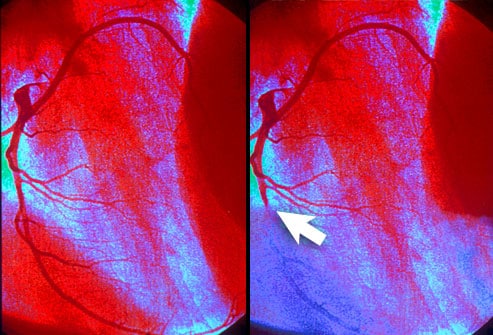

90% 이상의 경우, 바로 심혈관질병 치료법을 처방 하게 되며, 만일 환자에게 차도가 없을 경우나 불안정형 협심증 관련 증상이 보일 경우 바로 관상동맥 조영술을 권하게 된다.

위에 서술한 방법들로 협심증으로 진단이 내려질 경우 카테터를 삽입하여 관상동맥 우회술이나 PCI가 필요한지 결정을 내리게 된다.

PCI의 경우 안정형 협심증을 치료 하는데 있어서 약물 치료 보다 더 우월하다는 결과는 관찰 되지 않았다고 한다. 하지만 주로 약물을 처방 한 후에도 협심증 증상이 지속적으로 보여 지거나, 약물들의 부작용 으로 인해 더이상 복용을 하지 못하는 경우 등에 한에 사용된다.